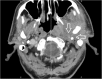

Background: Central skull-base osteomyelitis (CSBO) represents a life-threatening complication of external ear canal infection. Computed tomography (CT) and magnetic resonance imaging (MRI) play key roles in assessment of CSBO progression.

Methods: Twelve patients with CSBO were included in a retrospective clinical study. In total, 62 scans (30 CTs and 32 MRIs) were performed to evaluate the extent of inflammatory changes. The scans were read independently by two radiologists specialised in imaging of the head and neck. The regions under the skull base were specified using the online Anatomy Atlas of the skull base. To clarify the timeline, the time period was divided into four parts, and inflammatory changes in the skull-base regions were tracked. Data were statistically analysed.

Results: In early stages of the disease, CT scan detects inflammatory changes closely related to the stylomastoid foramen and medially to the posterior belly of the digastric muscle, changes which have been proved to be crucial for the diagnosis of CSBO. Later the infection spreads to the contralateral side causing demineralisation of the bones.